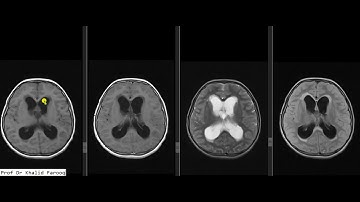

Neuro CT Quality (Part I/III of Brian Nett AOCNR 2021 talk)